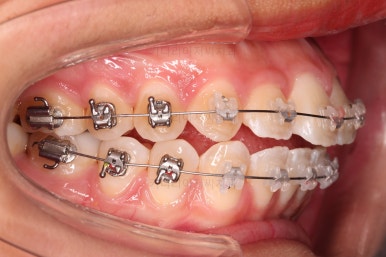

5. 마무리와 치료 종료

마무리가 잘 되었습니다.

큰 문제는 없었지만, 약간 삐뚤었던 치열이 가지런하게 정렬이 잘 되었고요.

맞물림도 매우 좋고, 뻗친 앞니 각도도 매우 좋아졌습니다.

입 안의 모습만 보면 최상급의 마무리가 되었고요.